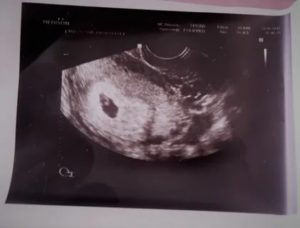

В 6 недель вынашивания эмбриона при проведении ультразвукового исследования на фоне утолщенного гиперэхогенного эндометрия определяется плодное яйцо. Оно представляет собой округлое или овальное анэхогенное образование с гиперэхогенным ободком.

В плодном яйце уже должны визуализироваться эмбрион и желточный мешок. Располагаясь эксцентрично, они формируют изображение на мониторе в виде двойного пузырька. Желточный мешок определяется как округлое тонкостенное образование с анэхогенным содержимым внутри.

Эмбрион определяется через 3 недели после зачатия. На шестой неделе он имеет вид головастика. Хотя многие органы уже закладываются, выявить пороки и аномалии развития эмбриона не представляется возможным.

Визуализация плода на первых неделях беременности затруднена. При исследовании врач обнаруживает зародыша и желточный мешок. На экране видны две едва уловимые тени. Отдельные части будущего человека на таком сроке рассмотреть невозможно.